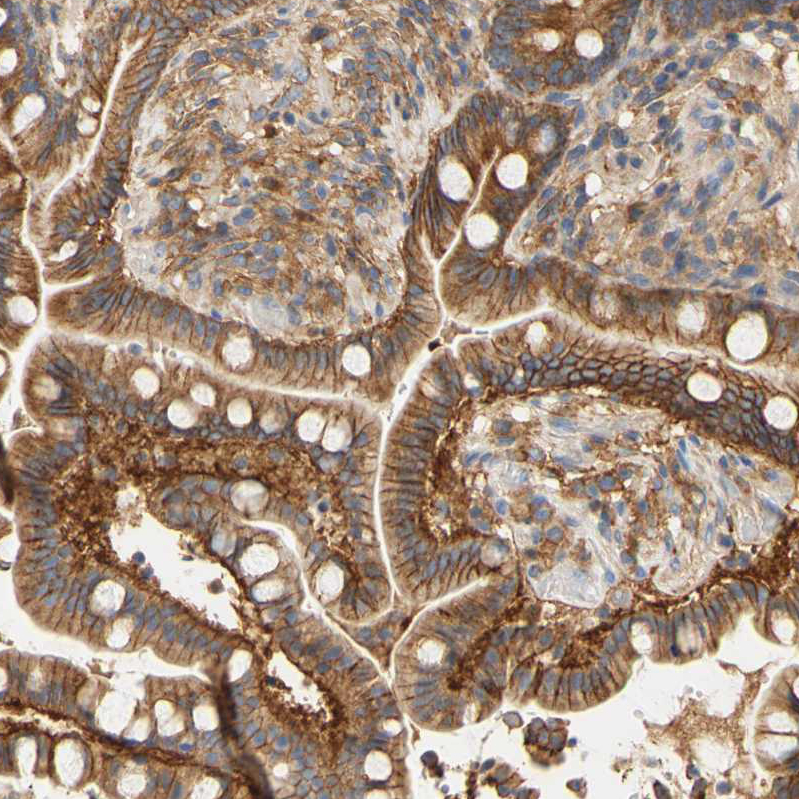

Immunohistochemical staining of human colon shows strong membranous positivity in glandular cells.